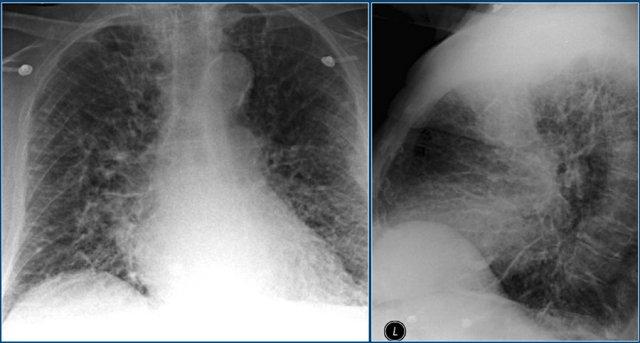

Sarcoidosis giai đoạn muộn

Đây là phim X-quang ngực thẳng điển hình của bệnh nhân mắc sarcoidosis giai đoạn muộn (giai đoạn IV).

Có xơ hóa ở vùng phổi trên.

Chẩn đoán phân biệt bao gồm viêm phổi quá mẫn mạn tính, cũng gây xơ hóa với ưu thế ở thùy trên.

HRCT cho thấy các đám mờ ở cả hai thùy trên.

Chúng được gọi là khối hợp lưu (conglomerate masses), là kết quả của sự tập hợp các nốt.

Đây là một bệnh nhân khác mắc sarcoidosis.

Có mất thể tích ở thùy trên do xơ hóa.

Hình ảnh bên trái cũng cho thấy các đám mờ trong phổi.

Trên HRCT thấy các nốt mịn.

Phim X-quang ngực thẳng theo dõi cho thấy hầu hết các bất thường phổi đã được hấp thu.

Xơ hóa vẫn còn tồn tại.